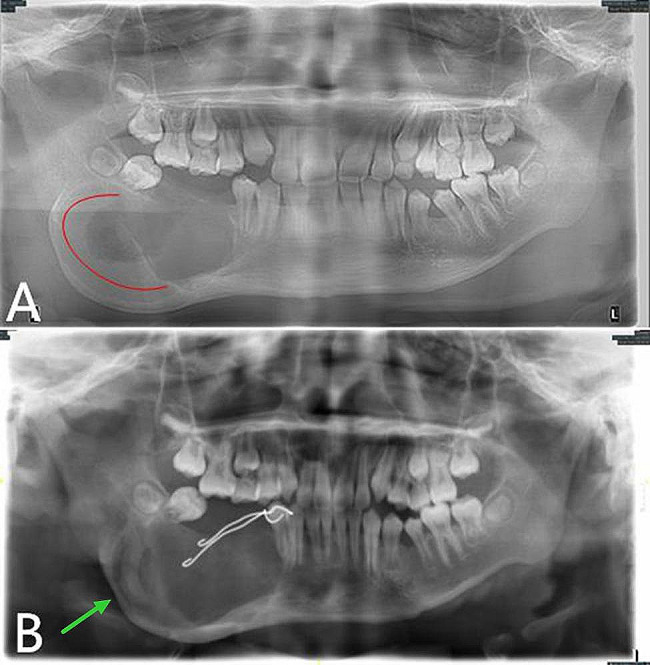

The right face and mandibular angle area were dilated, the skin color and temperature were normal, the mouth opening was limited, and there was no numbness in the lower lip. The right mandibular posterior tooth vestibular sulcus and ascending branch were seen in the mouth, the palpation was hard, there was no ping-pong-like sensation, the mucous membrane was intact, and the tooth 46 was II °loose. As shown in Fig. 1, the preoperative panoramic radiography revealed a typical AM: multilocular cystic low-density shadow of different sizes, overlapping each other, clear boundaries, and AM-involving teeth with truncated root resorption.

Fig. 1.

Preoperative panoramic radiography showing a typical AM in the right mandible

The reexamination 6 months after the operation showed that the low-density shadow in the jaw became more significant compared with that 3 months ago, and the original osteogenic area partially disappeared (Fig. 3). Local recurrence was considered. Then on June 27, 2019, the right mandibular tumor was cured by intraosseous curettage combined with decompression under general anesthesia. During the operation, the original opening window was enlarged, the tumor was completely eliminated along the bone wall, and the ball drill was used to grind off part of the bone wall. Special attention was paid to protect the inferior alveolar neurovascular bundle. The intraoperative frozen pathological analysis confirmed AM. To stop bleeding, the bone cavity was packed with iodoform gauze. The postoperative paraffin-embedded section showed the same result as the one before operation.

Fig. 3.

Panoramic oral radiogram. A, 3 months after the operation. B, 6 months after the operation. The original osteogenic area (A, red curve) disappear compared with B